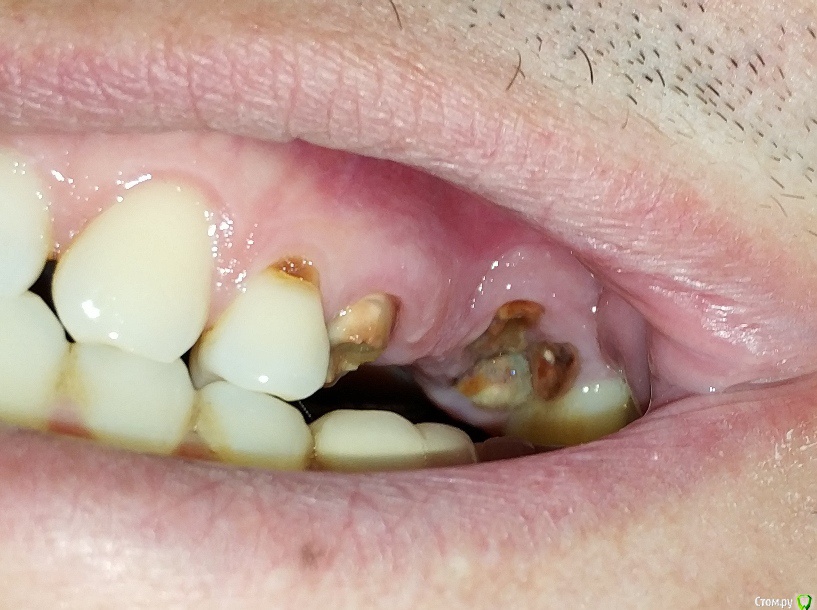

LTD Опубликовано 12 апреля, 2019 Поделиться Опубликовано 12 апреля, 2019 Мужчинка, 45 годов Слетел верхний мост 5-7 . Корень 7 (основание зуба ) отделился / разделился. «Целые» зубы 4, 8 не хочу трогать (обтачивать), решение зависит от бюджета. Просьба высказать мнение :а) Без имплантологии1 - делается ли вкладка на 7ку под дальнейший мост в таком состоянии? 2 - какие варианты восстановления возможны (съемные, бюгель и тд)?3 - какие варианты восстановления наиболее практичны по Вашему? б) хотя имплантация пока не по зубам Хочу понять:3 - на противоположной стороне 7-8 удачно стоит МК консоль на одном 7 зубе. Делается ли имплант с такой же конструкцией консоли на один 7-мой (который разрушен)?4 - делается ли одноэтапная имплантация на 7?5 - имеет ли смысл не удалять корни 7го с этой целью?6 - если 7 имплант + 567 мост (ставится ли мост - конструкция на 5й "свой") ?7 - возможность установки 7 без открытого лифта? Заранее спасибо! Ссылка на комментарий

krokomot Опубликовано 13 апреля, 2019 Поделиться Опубликовано 13 апреля, 2019 Вот могут же пациенты, себя хорошо сфотографировать, что всё видно и понятно, присоединяюсь к коллегам, но нижний зуб под коронкой тоже от жил свое... 2 Ссылка на комментарий

Doc Опубликовано 13 апреля, 2019 Поделиться Опубликовано 13 апреля, 2019 Вот могут же пациенты, себя хорошо сфотографировать, что всё видно и понятно, присоединяюсь к коллегам, но нижний зуб под коронкой тоже от жил свое...Современные телефоны снимают чуть ли не лучше, чем вся наша техника со вспышками прошлого века )) Кстати, топикстартер, расскажите на что снимали?! А по нижнему зубу да, я тоже заметил, но, как понимаю, человеку с верхними бы пока разобраться, не до низа. 1 Ссылка на комментарий